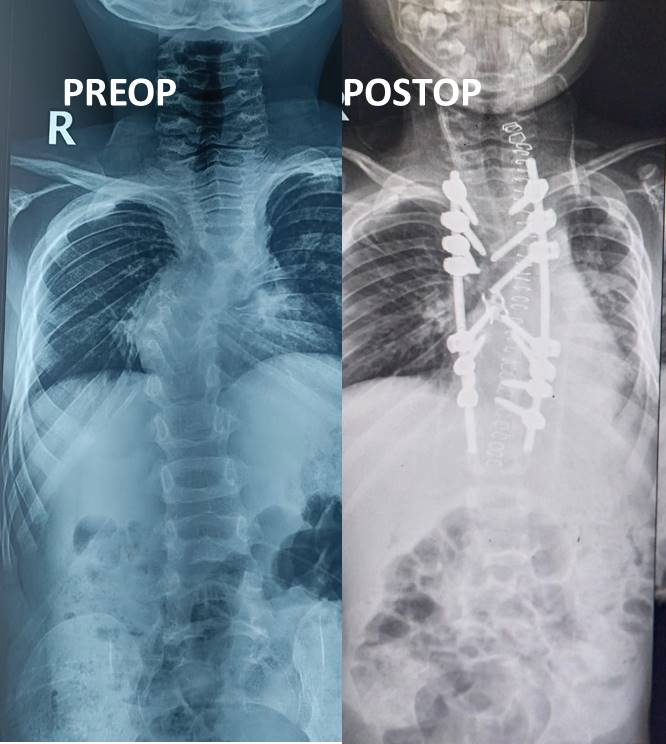

Case of Severe Congenital Kyphosis

At Verteva Spine & Ortho Care, we are dedicated to offering advanced solutions for the most severe and rare spinal deformities. This is the remarkable journey of a 7-year-old child diagnosed with severe dorsal congenital kyphosis , accompanied by spasticity and paraparesis.

• A 155° congenital kyphosis angle

• Kyphosis correction from 155° to 49°